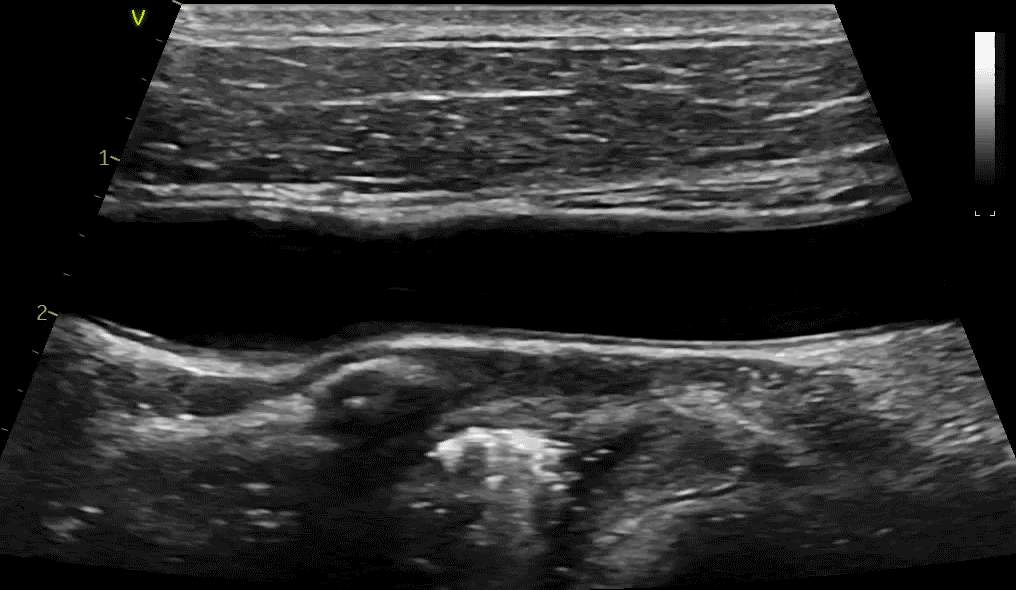

Gain innovative views into tiny structures - Acquire images on a wide range of pediatric and neonatal patients, quickly and with few system adjustments enabled by Dynamic Auto Optimization. Two dedicated pediatrics probes, 6S-D and 12S-D. Use XDclear™ transducers (C1-6-D and C2-9-D) to help you examine deep anatomy or shallow structures without sacrificing spatial or dynamic resolution.

Pediatric Color Flow

Blood Speckle Imaging**

Neonatal Heart Imaging